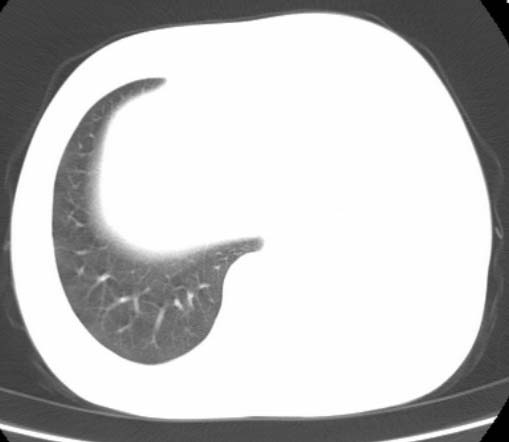

标题: CT25648:求教:是肺发育不全还是结核?

女  20岁。一月前咳血,诊“肺结核”抗痨治疗一月后,咳血停止,现复查。病人精神好。前后ct片对比未见明显变化。既往体检“正常”

1)考虑左肺结核并肺不张、支气管扩张。2)纵隔疝。

考虑左肺结核,左肺毁损,纵膈左偏,既往体检正常不可靠,tb一个月也不会这个样子的,有钙化,应该病程较长,冰冻三尺非一日之寒!

左肺发育不全。